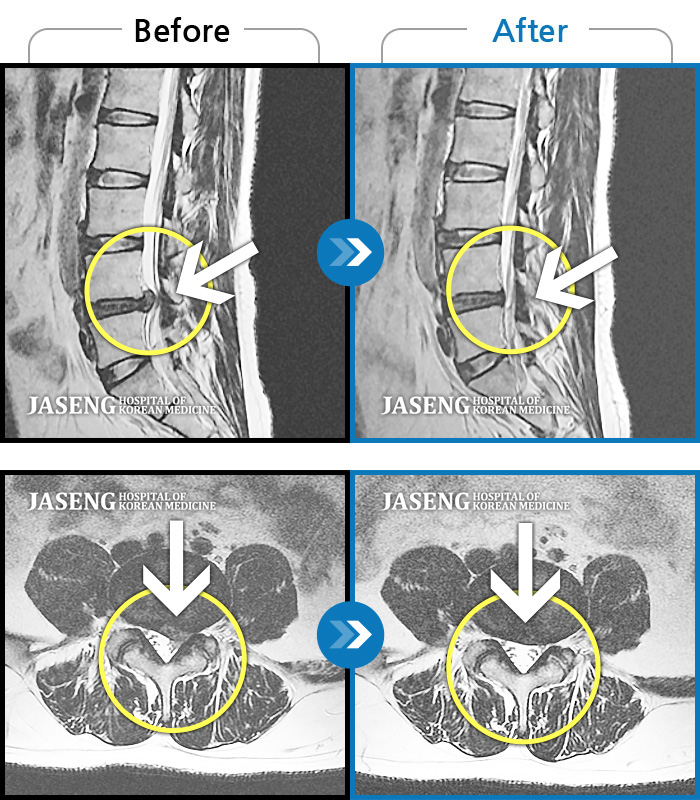

허리디스크

부천 · 신동재 원장

오른쪽 허리 골반 통증, 보행시 우측 다리까지 통증 및 당김 증상

촬영시기

2017.09.07 ~ 2018.12.07

2018.12.14

조회수 3,204